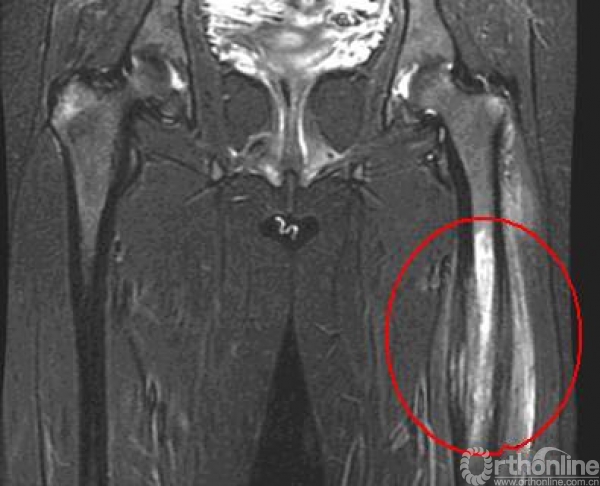

临床上常见反复发作,严重影响身心健康和劳动能力。急性骨髓炎起病时高热、局部疼痛,转为慢性骨髓炎时会有溃破、窦道形成、流脓、有死骨或空洞形成。重症患者可能会危及生命,有的不得不采取截肢的办法,致患者终生残疾。影像学和病理表现如下图。